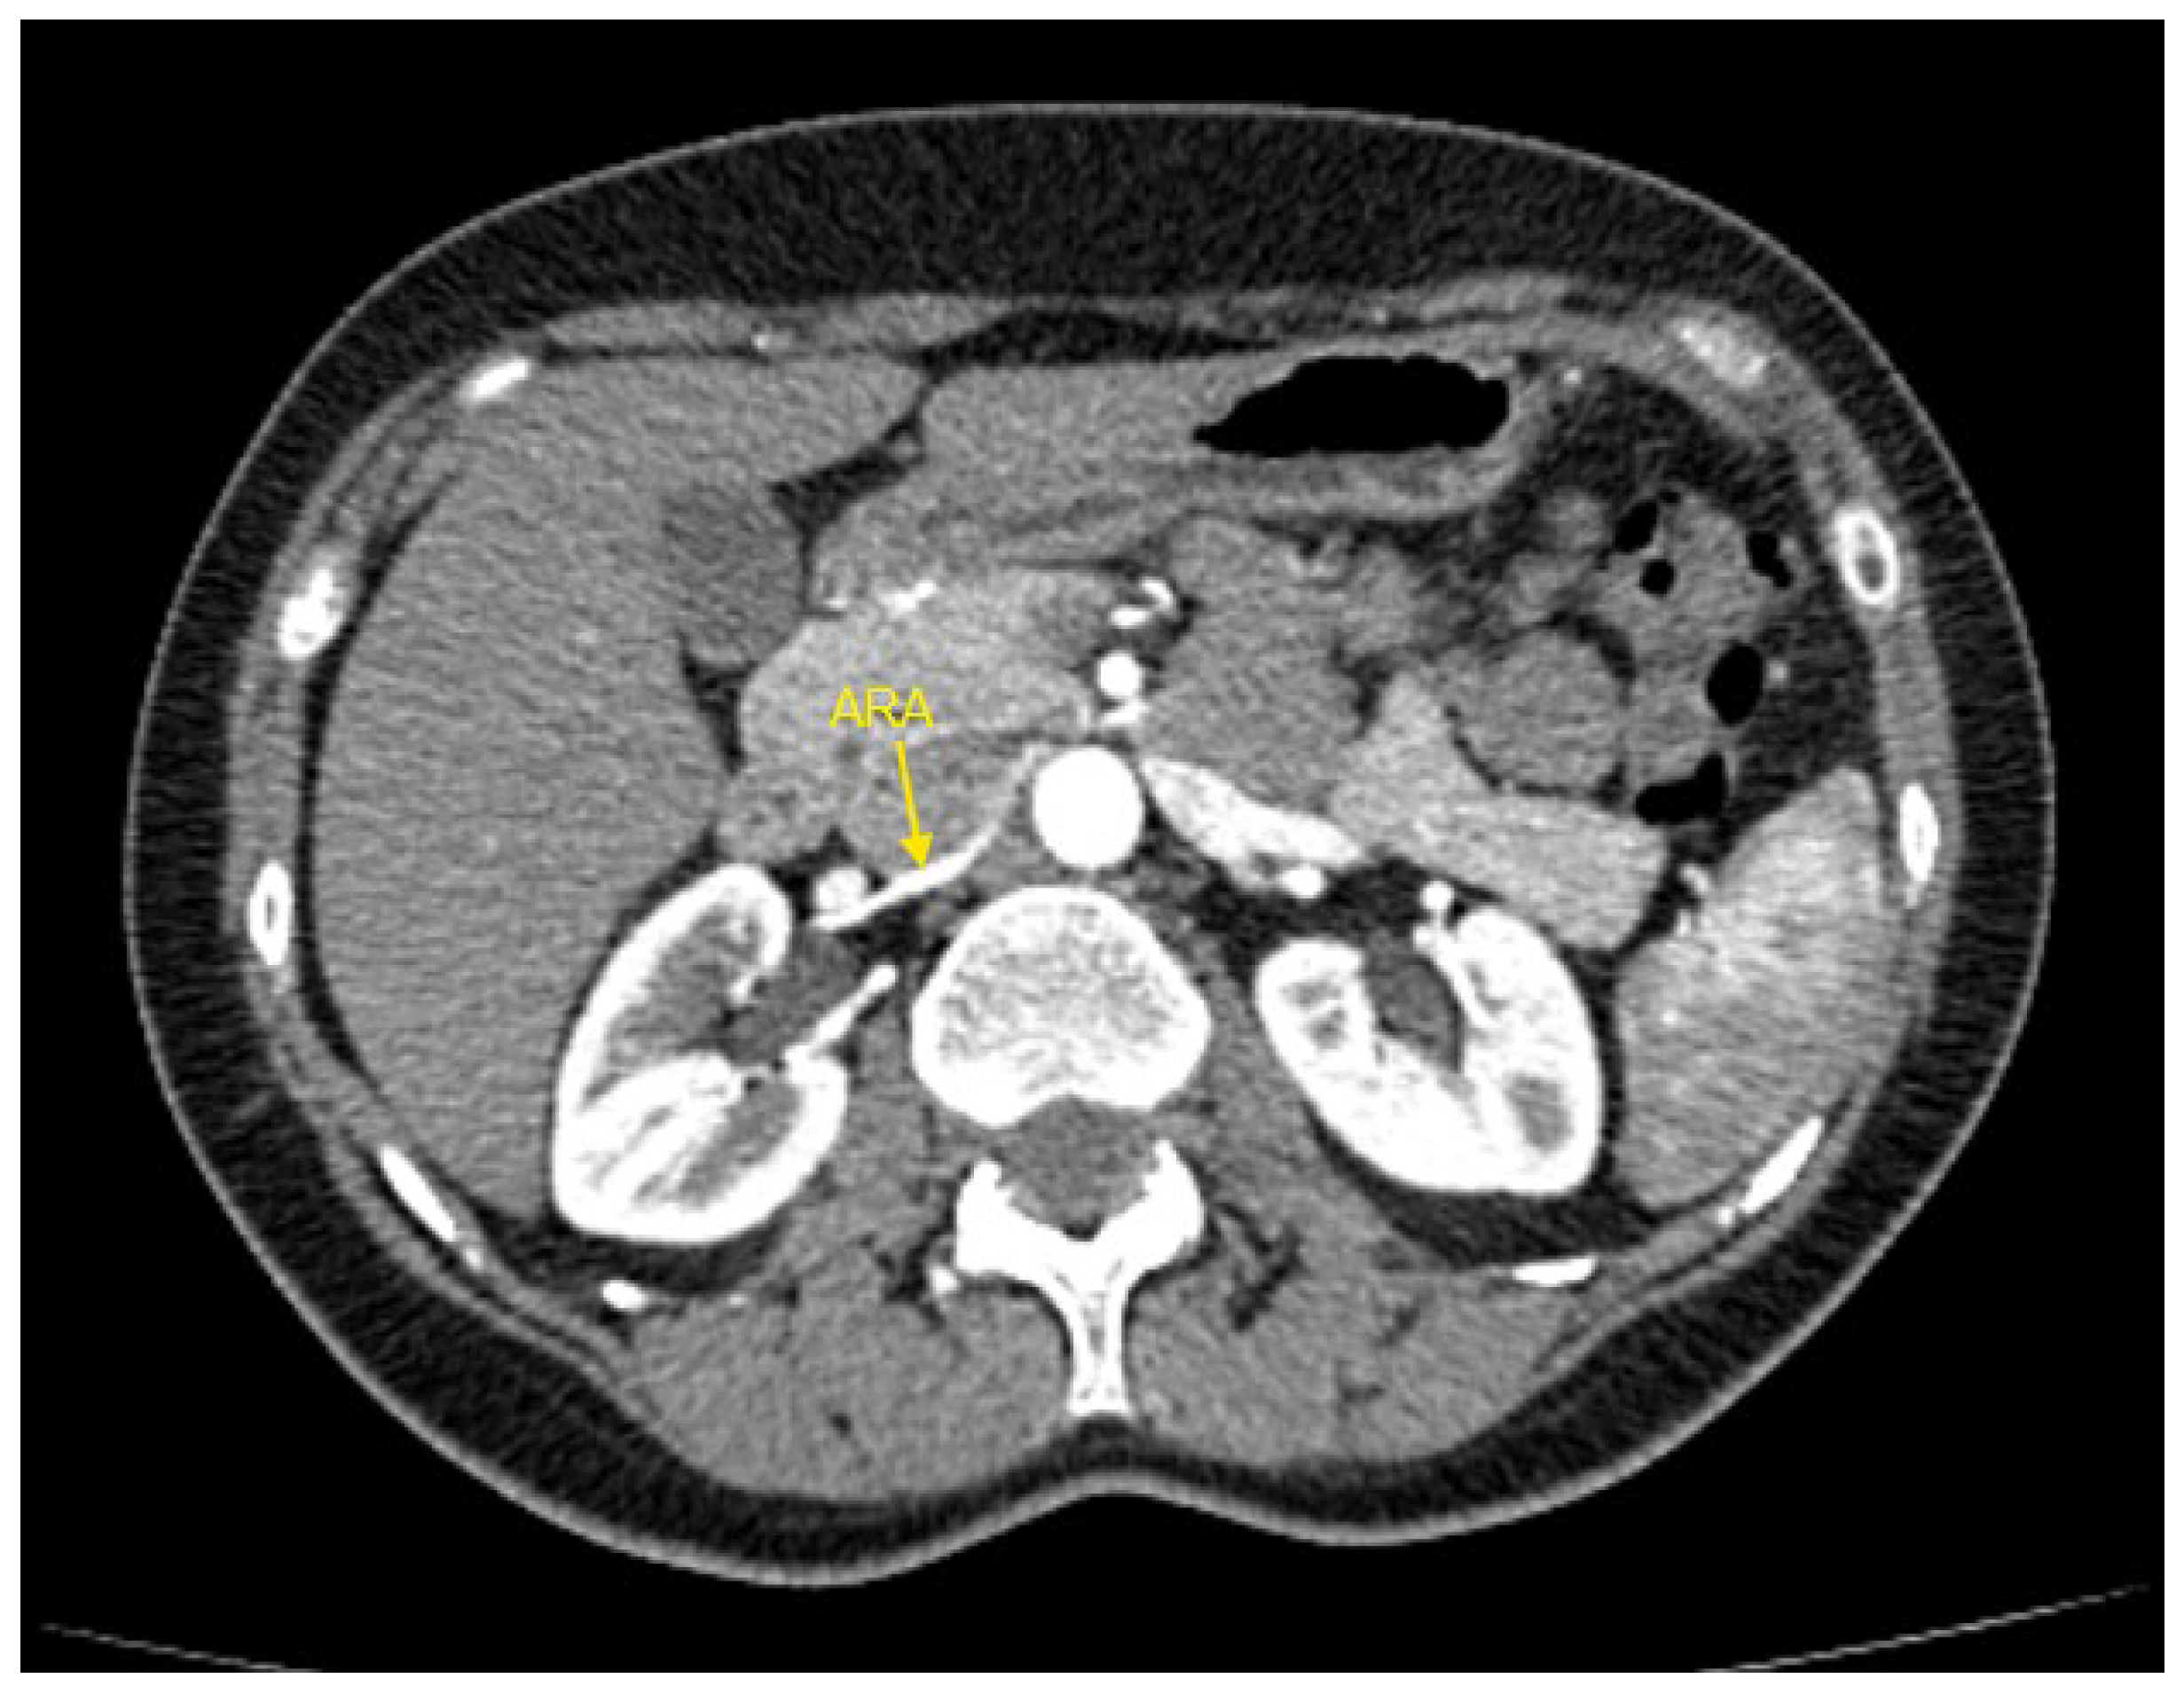

Figure 1, Figure 2, Figure 3, Figure 4 and Figure 5 show examples of some renal vascular abnormalities we identified in our study population.

Figure 3. Contrast-enhanced CT imaging of a 49-year-old female hypertensive patient failing to achieve blood pressure control by 4 drugs from different classes demonstrated an accessory renal artery in the right kidney, indicated by the yellow arrow. ARA—accessory renal artery; CT—computed tomography.